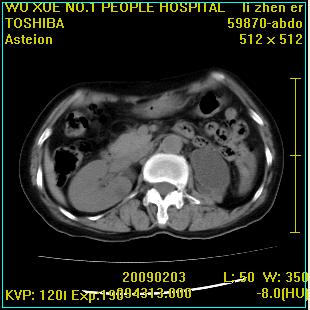

标题: CT18564:女,57岁,无不适,体验B超提示肾积水等 [打印本页]

标题: CT18564:女,57岁,无不适,体验B超提示肾积水等

左肾及左输尿管上端结石,左肾重度积水并左肾萎缩(不排除左肾先天性发育不良)。

左输尿管上端结石,左发育不良性多囊肾并积水;

右肾代偿性增大并肾盂积水,脾大。

左肾及左输尿管上端结石,基本上丧失肾功能了。

此患都左肾呈囊性变,边缘有高密度钙化,还是考虑结核吧.